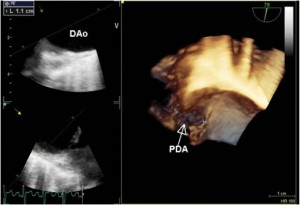

A 33-year-old man who had been diagnosed with PDA in childhood was refferedfor cardiac evaluation for fatigue and progressively worsening dyspnoea on exertion over the past 3 months. Physical examination revealed an afebrile patient, hyperdynamic precordium, a continuous murmur with thrill over the pulmonary area, peripheral oedema and hepatomegaly. The blood pressure was 120/60 mm Hg and the peripheral pulses were prominent. Auscultation of the lungs revealed mild basal crackles bilaterally. There were no clinical stigmata consistent with endocarditis. The ECG showed sinus rhythm at 78 bpm, biatrial abnormality, signs of left ventricular hypertrophy and complete right bundle branch block. There was no inflammatory syndrome or anemia. Transthoracic and transesophageal echocardiography confirmed the presence of a large PDA (defect size 11 mm), with a continuous systolic-diastolic flow signal with high velocities (up to 4.8 m/s) recorded by continuous wave Doppler examination at the level of this turbulent jet from the descending aorta to the pulmonary artery (Figures 1-3). The left ventricle was severely dilated (EDV/ESV=247/124 ml), with mild global systolic dysfunction (ejection fraction of 50%). The assessment of pulmonary artery systolic pressure was carried out by measuring peak tricuspid regurgitation velocity and the estimated value was 52 mm Hg. The TTE exam also revealed mobile vegetations on the pulmonary valve, with severe valve destructions, lack of coaptation and severe, free pulmonary regurgitation on color Doppler examination (Figures 4, 5). No vegetations were seen on the other valves, cardiac chambers or great vessels.

Figure 3. 3D TEE examination confirmed the existence of a large PDA (defect size 11 mm); PDA-patent ductus arteriosus, DAo- descending aorta.